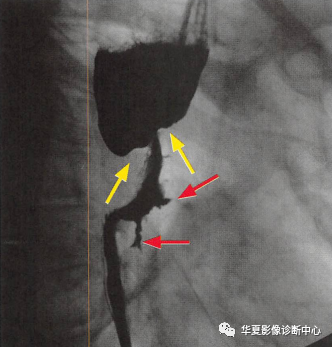

一定要小心食管的"黑色玫瑰花征"【YXZX093】

食管癌在鋇餐造影下的一種表現之一,顯示食管局部不規則狹窄(黃箭頭:玫瑰花花干),近端食管擴張(萎陷的玫瑰花朵),兩個不規則線狀潰瘍(紅箭頭:玫瑰花葉/刺),形似黑色玫瑰花,小編原創命名為:“黑色玫瑰花征”,幫助記憶,加深映像